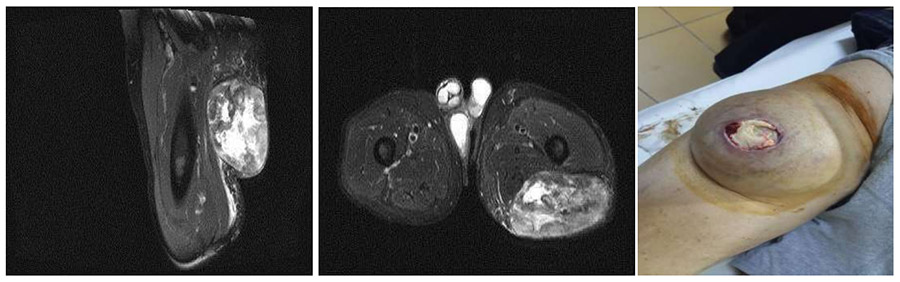

Ameliyat Öncesi: MR’da uyluk üst arka kısımda düzensiz sınırlı heterojen kitle ve klinik olarak cilde açıldığı görülmekte

Ameliyat Esnası: Çıkarılan tümör dokusu, ada flebinin hazırlanması ve yaranın kapatılması görülmekte